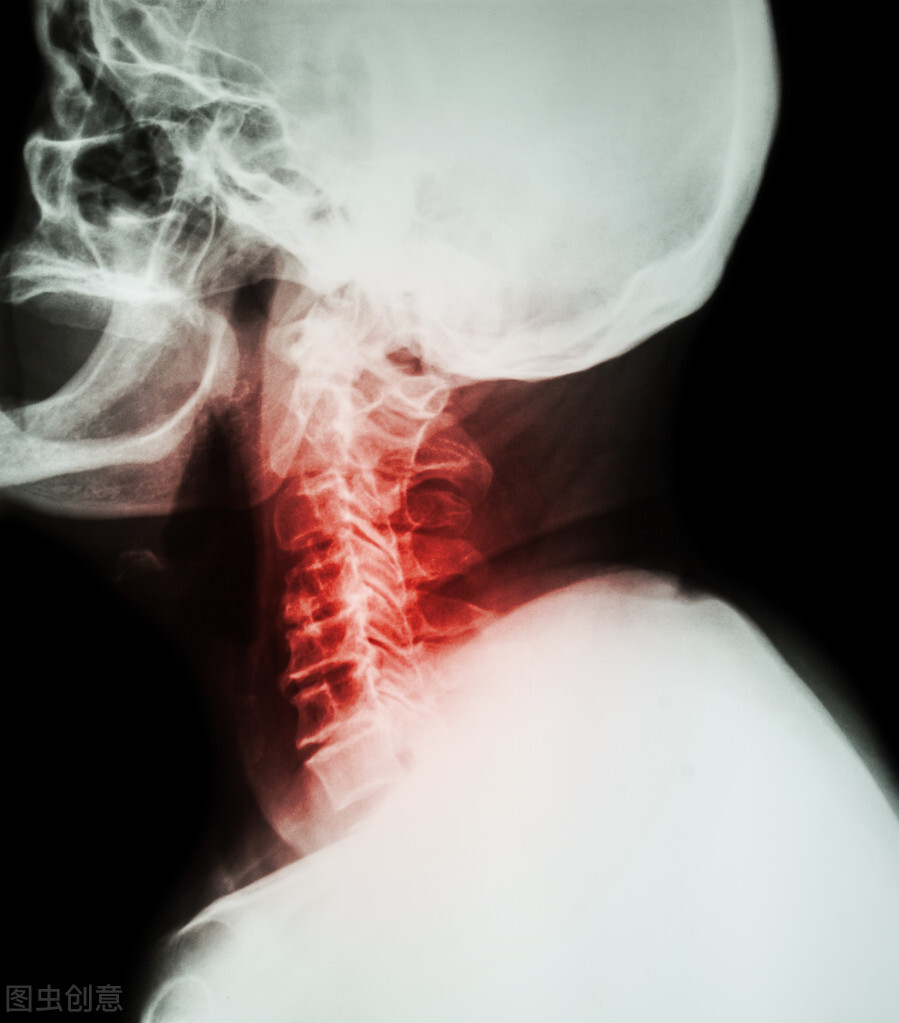

颈椎病是脊柱外科的常见病,我国成人患病率达到10%-15%,患者数量巨大,而不少人对于颈椎病还存在一定的认知误区,为了让大家更全面、科学地了解这一疾病,下面讲一下关于颈椎病的常见问题。

这种错误观念不只老百姓有,许多医生甚至某些骨科医生也这样认为。实际不然, 颈椎病的诊断至少要包括颈椎退变、造成压迫并引起相应症状3个要素,三者缺一不可。 许多中老年人甚至年轻人拍颈椎片子,一发现有骨刺,尽管没有任何不舒服,就被诊断为颈椎病了。其实,骨刺是年龄增大后人体的一种正常退变,但这仅仅是颈椎病诊断标准里的一条,还算不上颈椎病。另外,许多年轻人工作时间长了感觉脖子痛,拍颈椎X光片检查却没发现退变或压迫表现,也不能诊断为颈椎病,这往往是与职业或生活习惯有关的项背部肌肉劳损。所以,诊断颈椎病需要通过病史、X线检查和医生系统检查来综合判断。